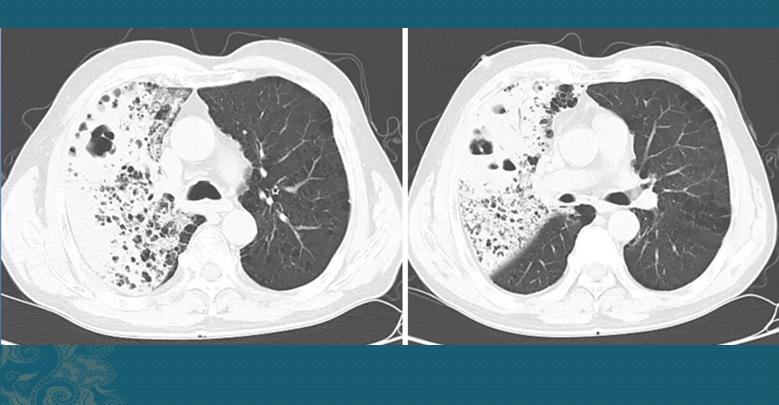

实际上,很多糖尿病人因为咳嗽、发热就诊,从胸部CT片上也能看出肺炎克雷伯菌肺炎的很多特点,这种肺炎分吸入性和血源性感染两种类型,其中血源性感染的病人常常伴有肝脓肿,是由于肠道里的克雷伯菌流窜到肝脏,失去管制大量繁殖,再通过血液入肺引起肺炎:

这是一位中年男子,多年糖尿病,比较倔强,血糖控制不太好,还经常喝点小酒,因为发热、咳嗽5天发现右肺大面积肺炎,伴有多发小空洞,有些空洞里有黏稠的脓液,因为比较稠厚不太容易咳出来,这是典型的肺炎克雷伯菌肺炎的CT表现。后来从痰液培养中发现大量肺克。